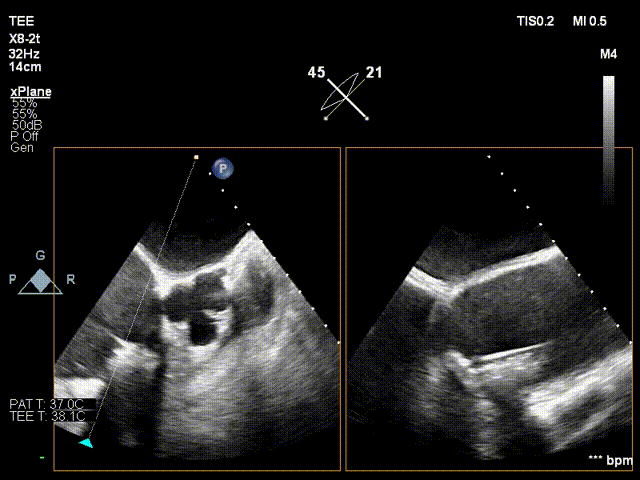

超声提示

影像分析

生物瓣金属内径28.9mm

面积折算直径21.6mm

周长折算直径21.8mm